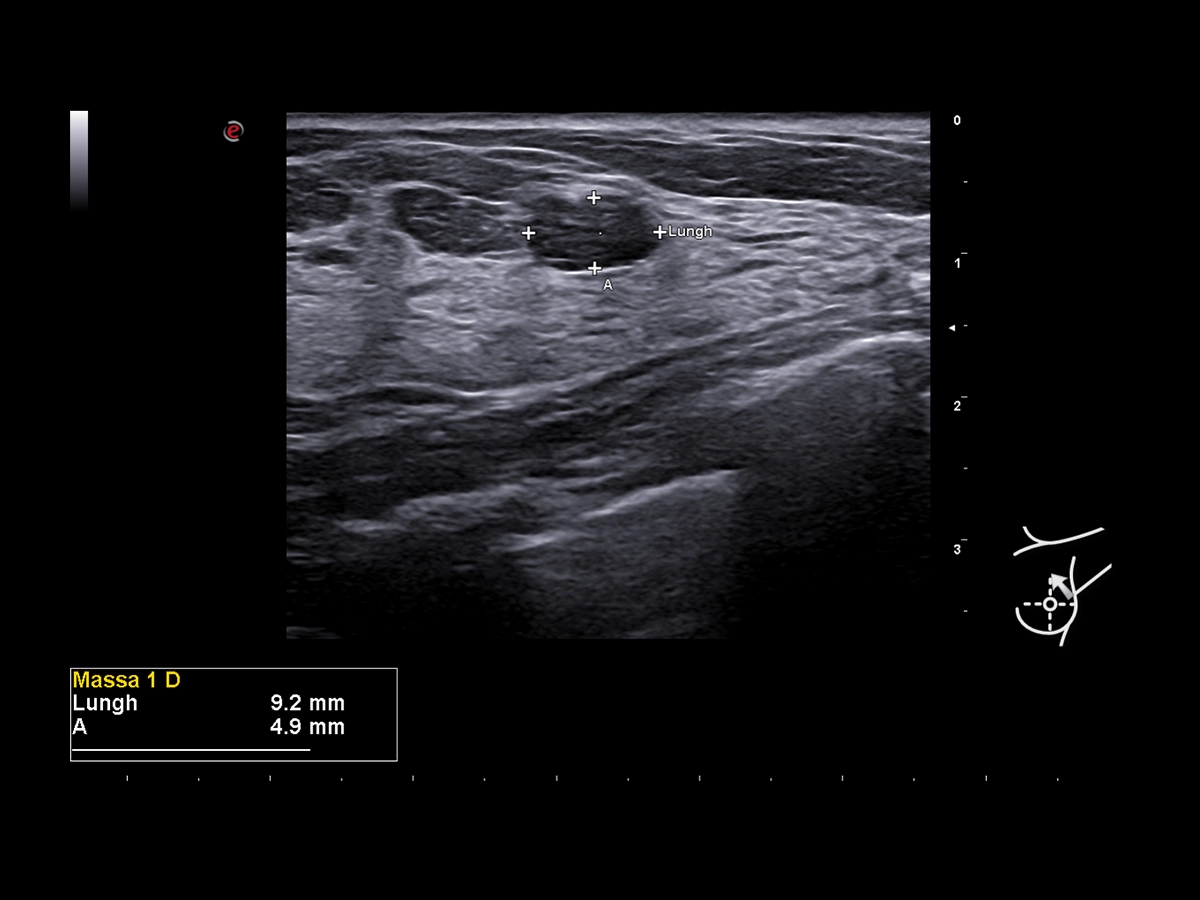

Breast Mass Analyzer (BMA), powered by A.I., is a machine learning model based on radiomics to predict the BI-RADS® category of ultrasound-detected suspicious breast lesions, support medical decision-making and reduce unnecessary biopsies. The A.I.-based eDetect algorithm provides automatic contouring of breast lesions and automatic measurements (P & A) of suspect areas. It also provides automatic cross-distance measurements of the lesions.

Breast clinical image